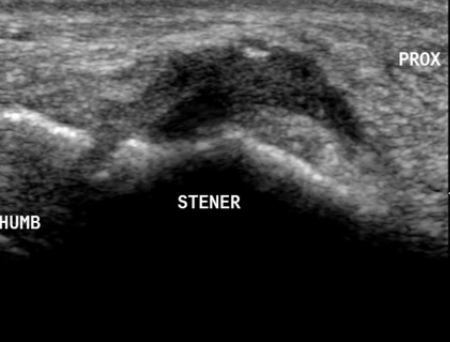

초음파상 검게 보이는 Stener 병변